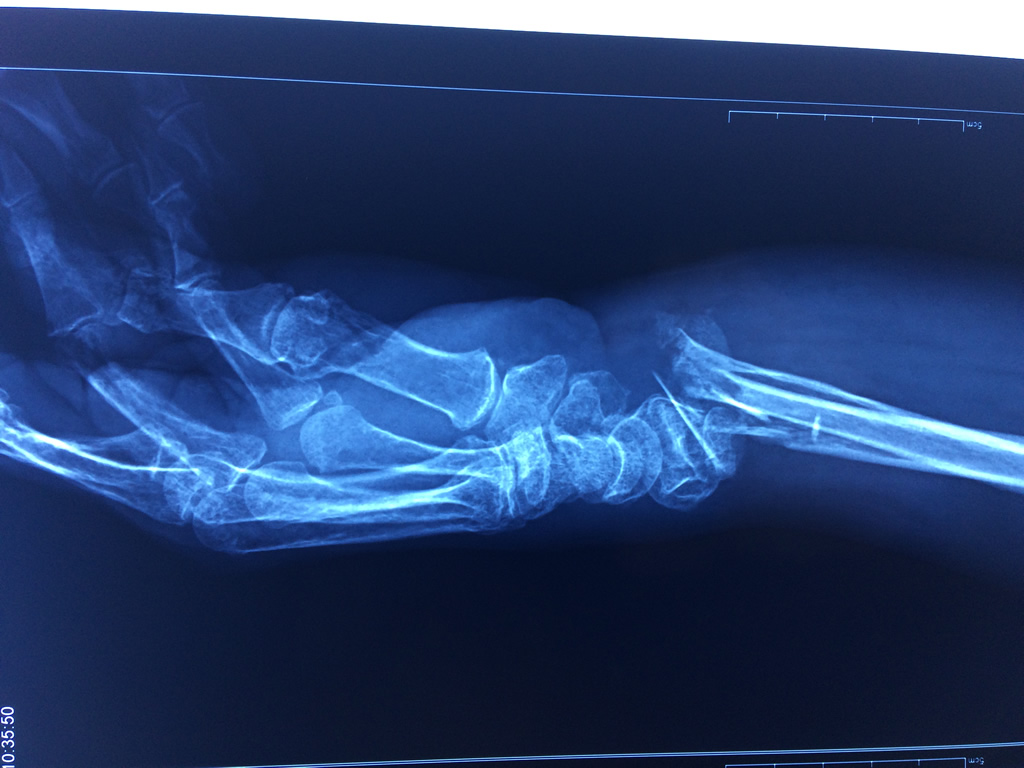

Cirugías de Húmero - Cirugías de Muñecas y Manos

Los procedimientos más comunes en cirugía de la mano son aquellos destinados a reparar traumatismos, incluyendo lesiones de tendones, nervios, vasos sanguíneos, y articulaciones; huesos fracturados; y quemaduras, cortes, y otros daños de la piel.